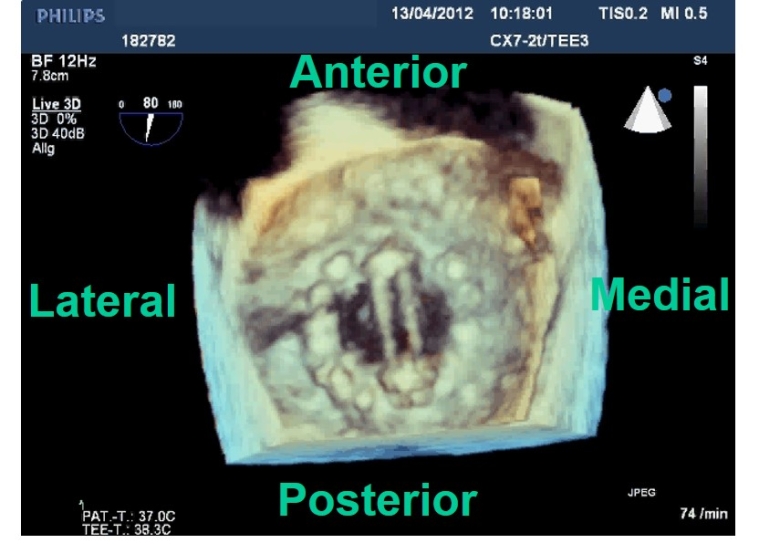

The orientation of a bileaflet MHV influences intraventricular haemodynamics. An anti-anatomic orientation (the MHV hinge line oriented towards the left ventricular [LV] outflow tract and not parallel to the commissure line of the native valve) is associated with a more favourable LV flow pattern [2]. This MHV positioning redirects the LV inflow towards the LV outflow tract and may avoid unfavourable effects on LV energy kinetics and decrease the risk of thrombus formation (Figure 1).

Figure 1. Three-dimensional transoesophageal echocardiographic image of a mechanical bileaflet mitral valve, viewed en face from the left atrial side (surgical view) in diastole with the leaflets in the open position. Please note the anti-anatomical position of one lateral and one medial leaflet with the hinge line oriented towards the left ventricular outflow tract and not parallel to the mediolateral commissure line of the native valve.